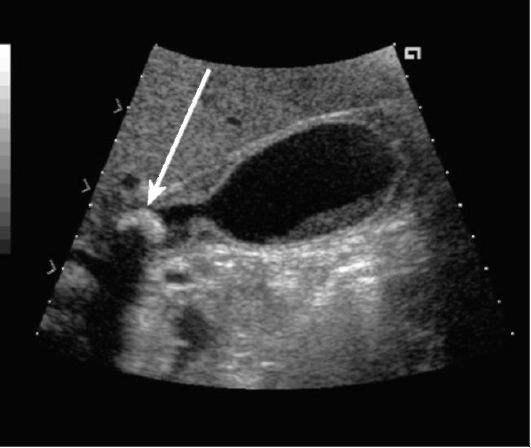

- начало формирования конкрементов. Врачи называют этот период латентным каменоносительством. Внешне заболевание не проявляет себя, но при проведении дополнительного обследования, становится понятно, что в желчном пузыре человека присутствуют конкременты;

- латентная форма. Больные не на что не жалуются, каких-либо изменений в самочувствии не отмечено. Во время ультразвукового обследования выявляется какое-то количество камней, которые чаще всего имеют холестериновый состав. Такая форма является характерной для мужской части населения;

Регулярно проходите медицинские обследования: особенно если у вас есть предрасположенность к заболеваниям желчевыводящих путей. Ультразвуковое исследование может помочь выявить камни на ранней стадии и предотвратить осложнения.